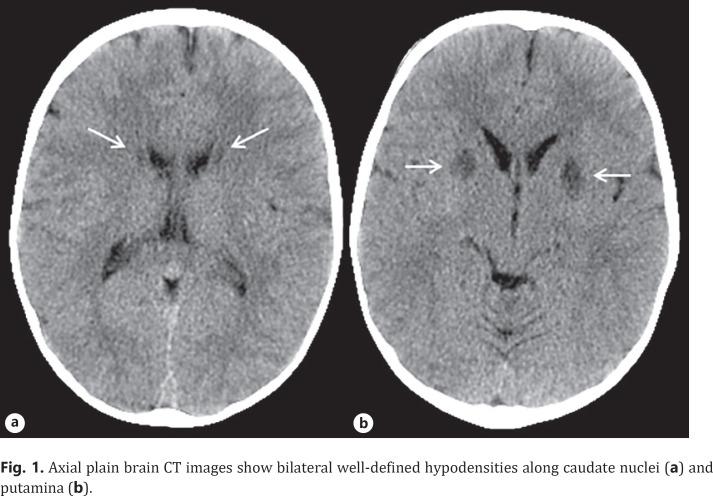

MEGDEL 3-methylglutaconic (MG) aciduria, deafness, encephalopathy, Leigh-like syndrome is an autosomal recessive disorder associated with infantile hypoglycemia, progressive psychomotor developmental delay, cerebellar atrophy with lesions in the basal ganglia, spasticity, dystonia, deafness, and transient liver problems, which typically occur in the first year of life. Other clinical presentations include failure to thrive, epilepsy, and optic nerve atrophy. The serine active site-containing 1 (SERAC1) mutation is localized at the mitochondria-associated membranes, which are responsible for encoding a phosphatidylglycerol remodeler essential for both mitochondrial function and intracellular cholesterol trafficking and is thus responsible for the disease. Diagnosis is confirmed by the elevation of and concentrations of 3-MG acid and 3-methylglutaric acid in the urine or by identification of bi-allelic SERAC1 pathogenic variants on molecular genetic testing. Different pathological variants of SERAC1 have been identified in MEGDEL syndrome to date. Here, we report a case of a child with MEGDEL syndrome due to SERAC1 mutation. The child presented with accidental finding by CT showing hypodensity on bilateral symmetric anterior putamen and caudate abnormal. Neurological examination was unremarkable. This report presents a new neuroimaging finding by CT of MEGDEL syndrome.

MEGDEL综合征(3-甲基戊二酸(MG)尿症、耳聋、脑病、类 Leigh 综合征)是一种常染色体隐性疾病,与婴儿期低血糖、进行性精神运动发育迟缓、伴有基底神经节病变的小脑萎缩、痉挛、肌张力障碍、耳聋以及短暂性肝脏问题相关,这些症状通常在出生后第一年出现。其他临床表现包括生长发育迟缓、癫痫和视神经萎缩。含丝氨酸活性位点1(SERAC1)突变定位于线粒体相关膜,该膜负责编码一种对线粒体功能和细胞内胆固醇转运至关重要的磷脂酰甘油重塑酶,因此是导致该疾病的原因。通过尿液中3-MG酸和3-甲基戊二酸浓度升高或分子基因检测中双等位基因SERAC1致病变异的鉴定来确诊。迄今为止,在MEGDEL综合征中已鉴定出SERAC1的不同病理变异。在此,我们报告一例因SERAC1突变导致的MEGDEL综合征患儿病例。该患儿通过CT偶然发现双侧对称的前壳核低密度以及尾状核异常。神经系统检查无明显异常。本报告展示了MEGDEL综合征CT检查的一项新的神经影像学发现。